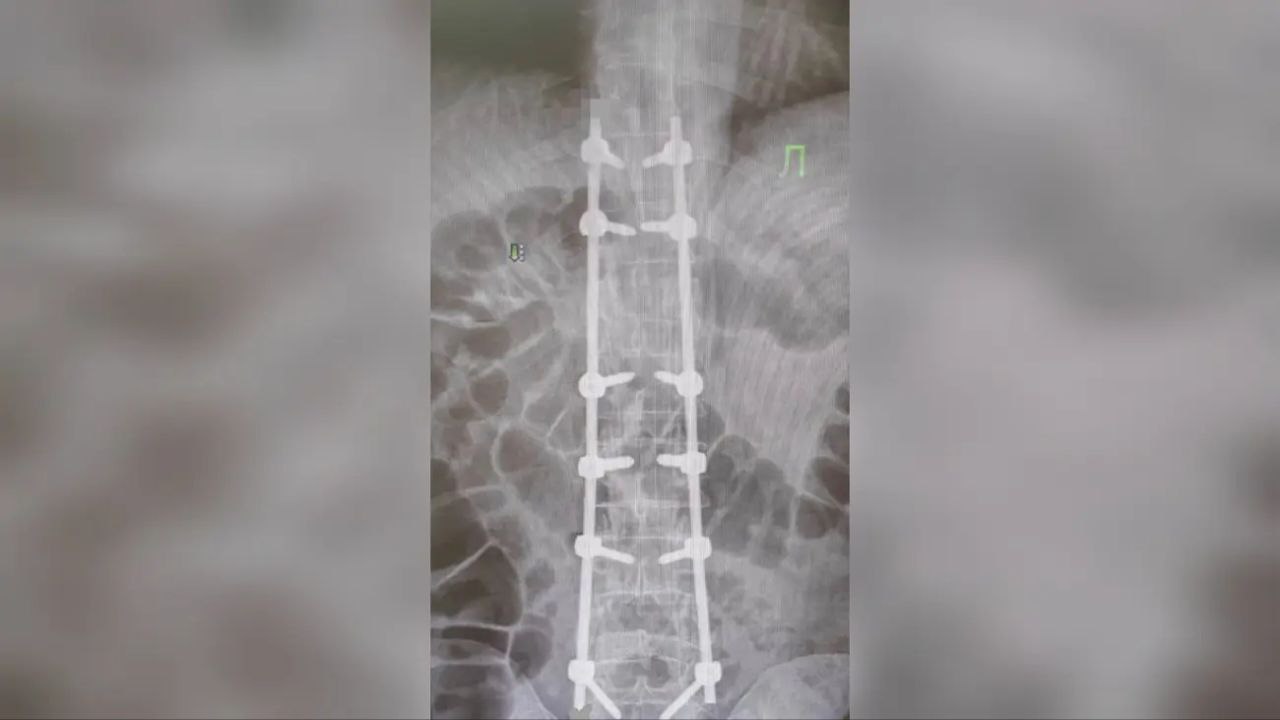

Во время вмешательства был использован метод хирургической стабилизации позвоночника. Через специальные анатомические структуры — ножки позвонков — в повреждённые сегменты были установлены титановые винты, соединённые прочными металлическими стержнями. Конструкция создаёт надёжный внутренний «корсет», который фиксирует позвоночник, снимает давление с нервных структур и способствует восстановлению костной ткани.